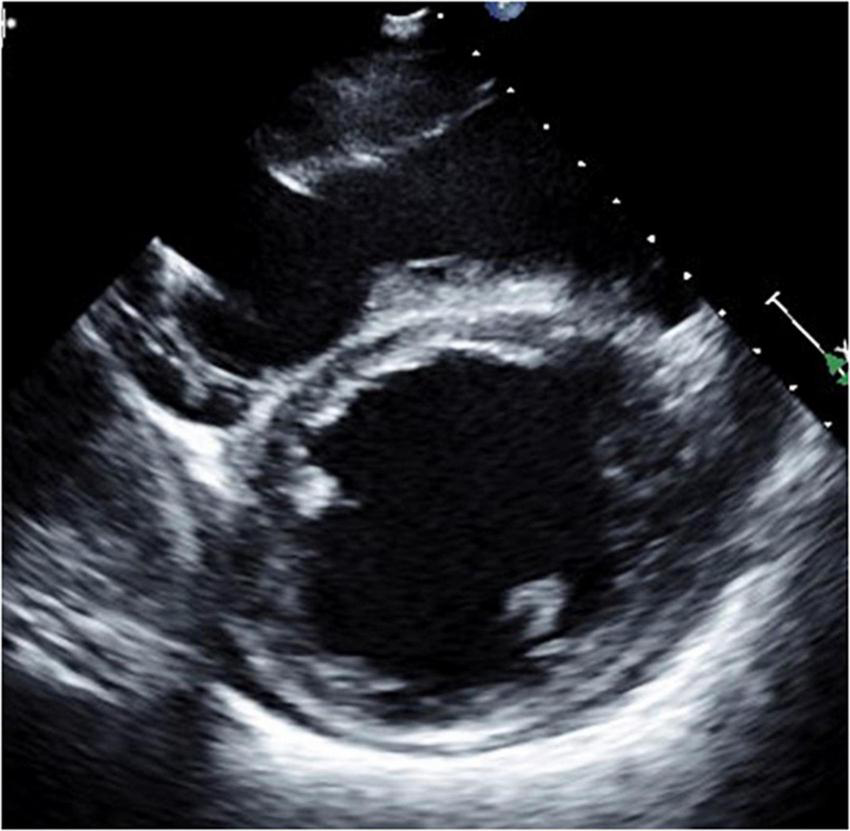

FIGURE 5

Long-axis view at end-diastolic phase of transthoracic echocardiography in Case 3. Note that the right ventricle is much larger than the left ventricle, and the left ventricle is very small (end-diastolic dimension 31 mm).